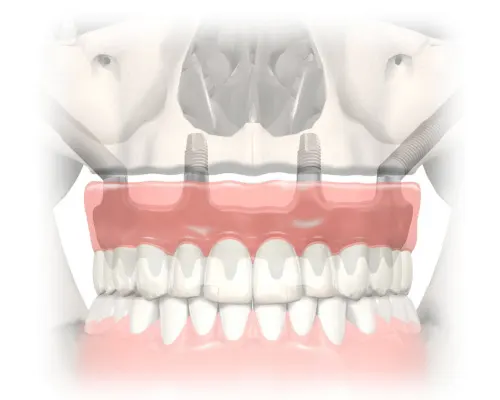

Zygoma dental implants or zygomatic implants are done for the edentulous upper jaw where there is severe bone resorption in the maxilla (or upper jaw) where bone condition has insufficient anchorage for prosthesis (fixed bridges or overdentures). The zygomatic dental implants provide such cases with a permanent solution involving minimal surgical procedures at reduced treatment time, without sacrificing their expectations of success. Zygoma implant presents a unique alternative for rehabilitating the severely resorbed maxilla, with only one surgical procedure and without the need for

With the zygoma dental implant technique, teeth is extraction and the implant post placed during the same surgical visit. A fixed acyrlic bridge is fabricated and functioning within 1 to 2 days after surgery. The timeline for zygoma dental implants is thus completed within one trip.